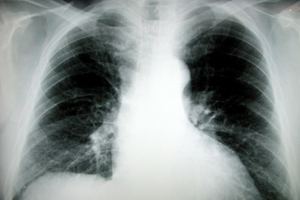

Первая в истории трансплантация новой трахеи, выполненной из синтетических материалов с использованием стволовых клеток пациента, была произведена в Швеции. Операция прошла 9 июня 2011 года в больнице Каролинского университета Стокгольма под руководством профессора Паоло Мачьярини (Paolo Macchiarini). Пациентом был 36-летний мужчина, страдавший от поздней стадии рака трахеи. Несмотря на активное лечение и лучевую терапию, его опухоль достигла к тому моменту около 6 см. в длину. Заболевание быстро прогрессировало, и трахея оказалась практически полностью заблокирована. К сожалению, подходящего донора не оказалось, и единственным шансом для мужчины стала пересадка синтетического органа.

Итак, межнациональная команда специалистов под руководством профессора Мачьярини при помощи нанотехнологий построила этим летом своеобразный макет трахеи из синтетического материала. После этого у пациента были взяты стволовые клетки, которые в специально разработанном «биореакторе» были подсажены на каркас органа. В течение двух дней была достигнута необходимая для трансплантации кондиция искусственной трахеи. Благодаря тому, что использованные для регенерации органа клетки принадлежали самому больному, они не вызывают отторжения и принимаются организмом «за свои», а пациенту не нужно пить вредные иммунодепрессанты. Более того, мужчина находится на пути к полному выздоровлению и уже выписан из больницы.